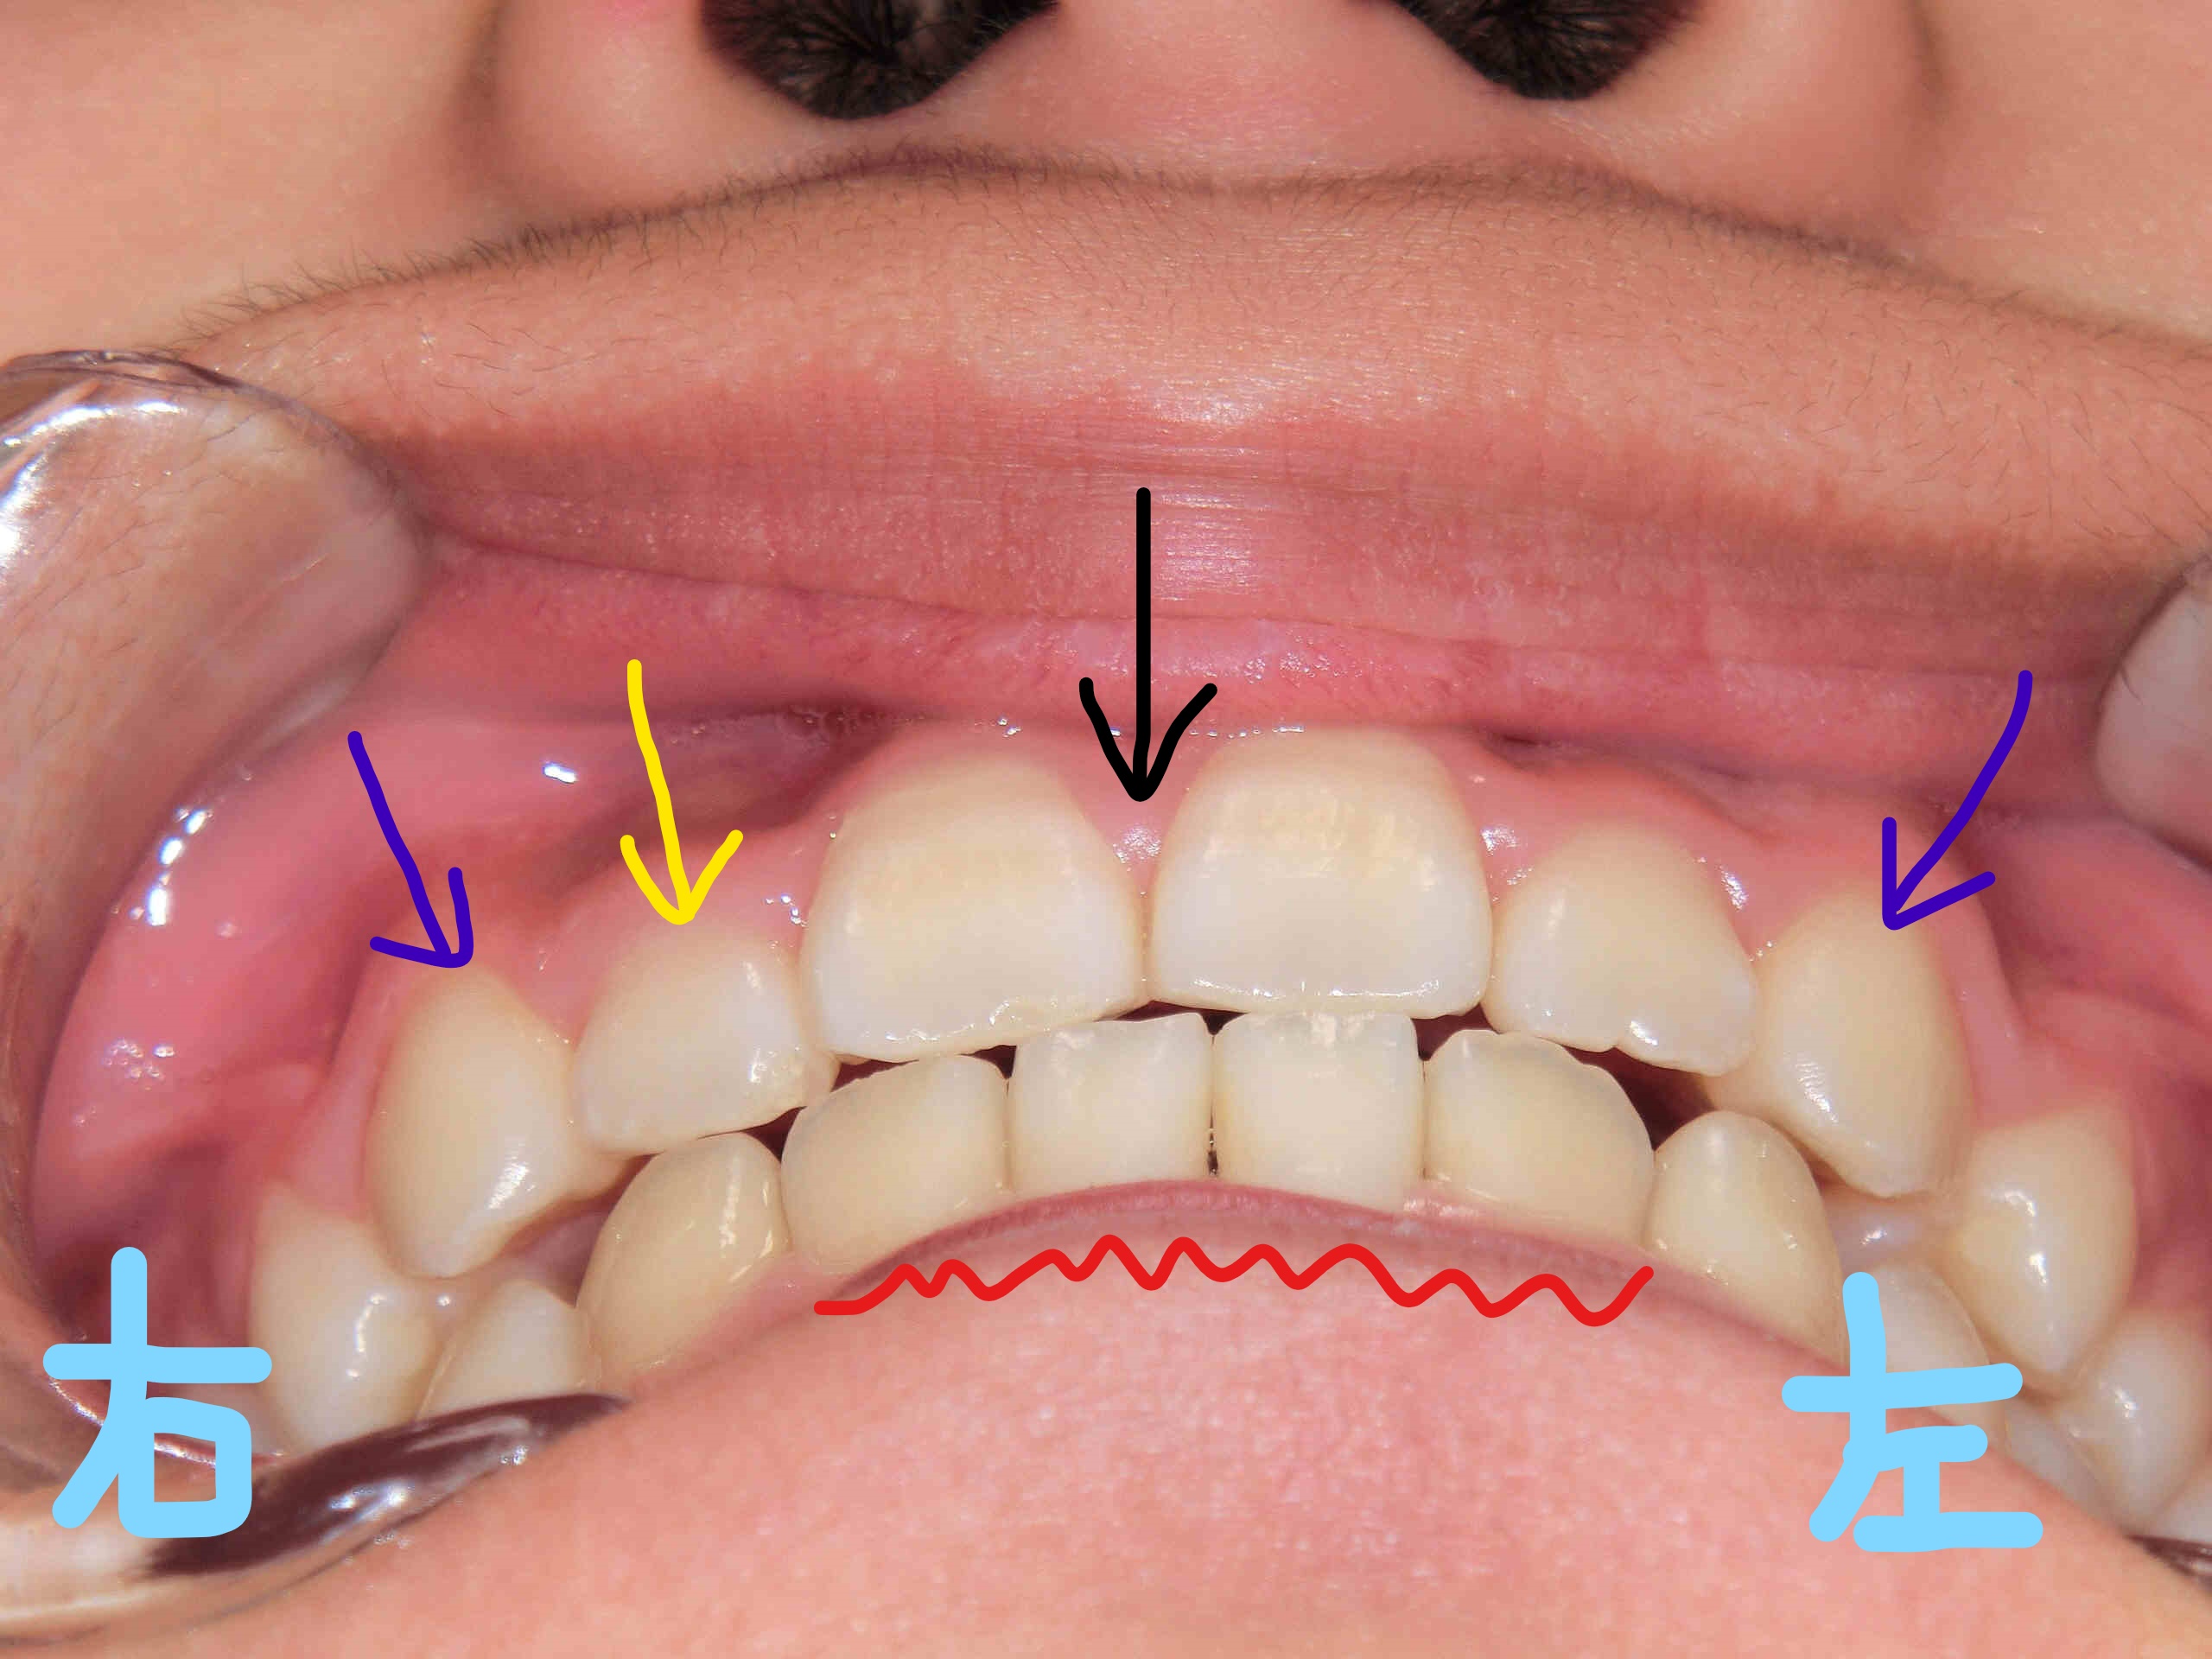

左上の写真は正面から見た状態、右上の写真は下から見上げた角度のものです。上顎前歯(黄色矢印)と両側の犬歯(紫矢印)が歯列内にきちんと収まっている様子が確認できます。

また、以前に固定式の拡大装置(急速拡大装置〈RPE〉)を使用して上顎を拡大した際に一時的にできた前歯間の隙間(黒色矢印)は、治療の経過とともに閉じてきています。